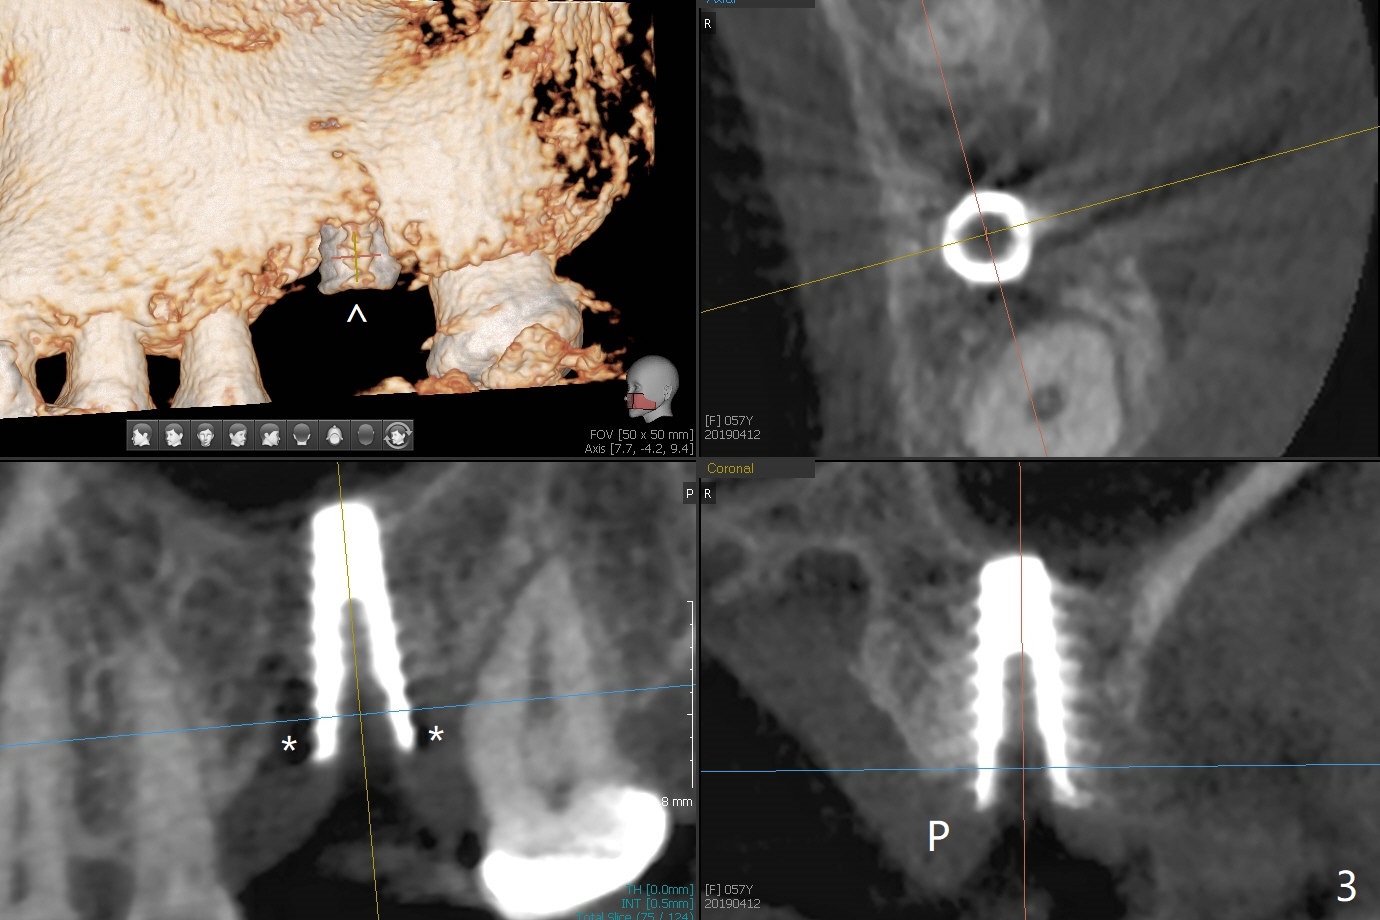

A 57-year-old woman complains of bad smell while use of water flosser between 11 and 21 months post cementation of implant crown at #14 (Fig.1,2). Bone loss is more obvious with CBCT (Fig.3,4), in spite of apparently normal gingiva around the implant after removal of the abutment and crown (Fig.5). In fact the buccal (B) gingiva is fragile with easy access to the underlying implant plateau. Following flap elevation, the bone loss is evident (Fig.6), but the implant plateau is slightly subcrestal (Fig.7 *). The exposed implant threads are covered with the 1st round of bone graft (Fig.8). After 2nd round of allograft (Fig.10-12) and collagen membrane, the flaps are approximated (Fig.9). The wound is covered by acrylic dressing. The latter is loose, but stays in place 1 week postop (Fig.13). Due to short neighboring teeth, the acrylic dressing is able to be removed with wiggling; it appears that the wound is healing (Fig.14). The dressing returns for another 2 weeks; some of the graft has been lost (Fig.15). The dressing does not return 7 weeks postop, since the wound is healing (Fig.16).